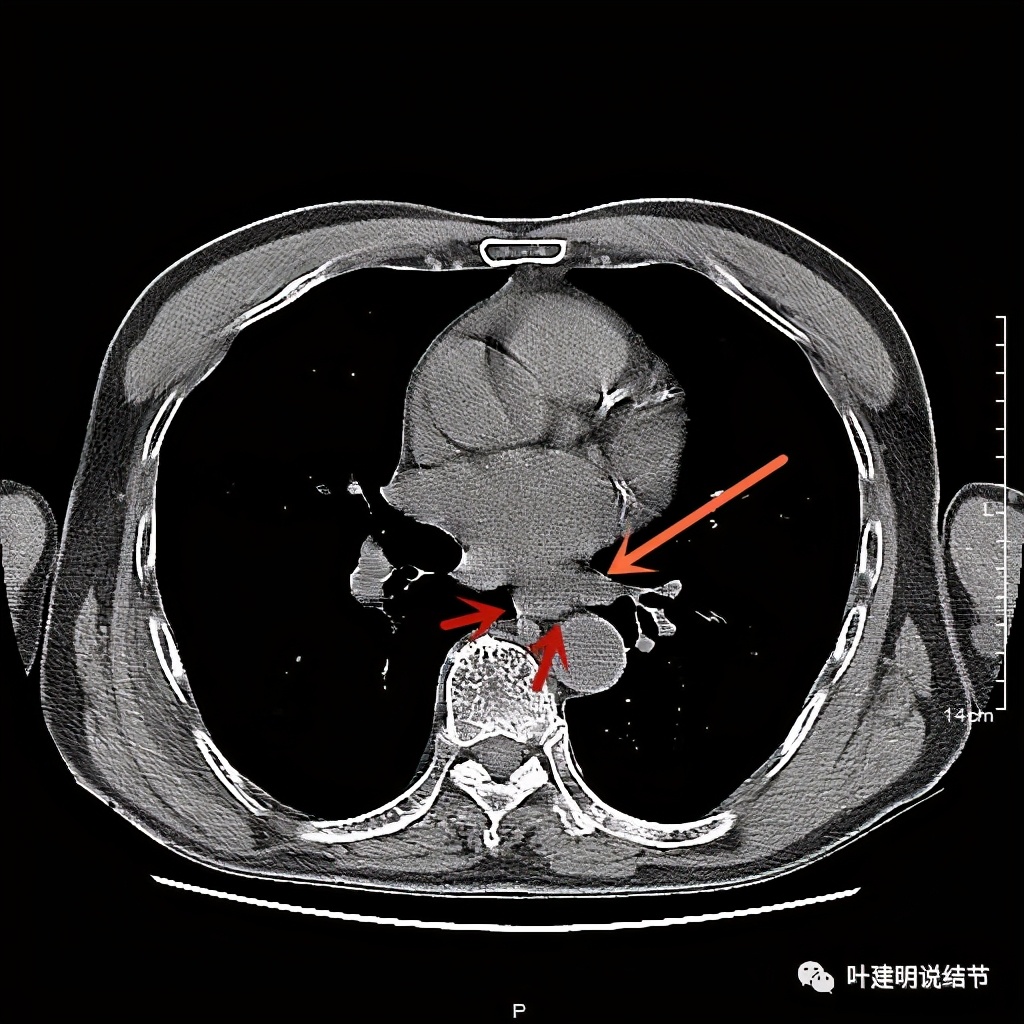

活检后食管是鳞癌,结肠是腺癌。下面是其术前CT的图像:

位于左下肺静脉水平

红色示肿瘤

红色示肿瘤,桔色示下肺静脉,与主动脉间间隙清楚